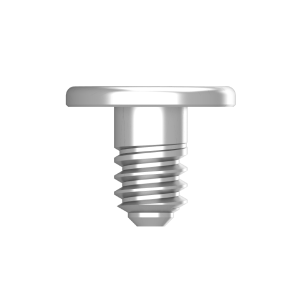

Enhanced fixation: Designed to be used with bone tacks for stable placement